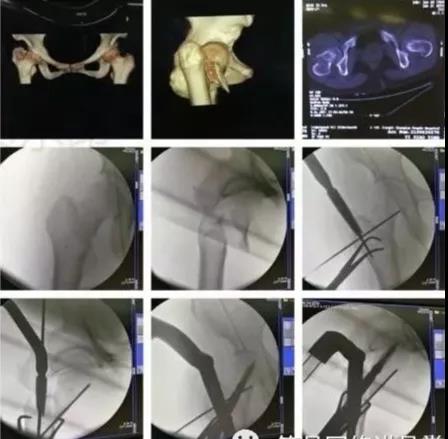

3)髋臼骨折(伤后5-7天)

- 人体最大的负重关节,精确复位可达到关节的最佳匹配,确保正常力学性能;

- 影像学移位程度大,不匹配>2mm--手术;

- 髋关节脱位,髋臼后壁骨折并股骨头骨折,复位后关节仍然不稳,或关节腔有游离骨块--手术。

并发症:异位骨化18-90%;股骨头坏死3-9%